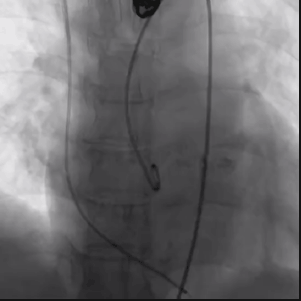

从三叶瓣重度钙化到二叶瓣畸形的根部解剖,从单纯主动脉瓣反流到入路极端迂曲挑战的案例。TaurusOne凭借其优异的柔顺性,支撑力强及内外层双侧裙边的特点,都能从容应对复杂的临床患者解剖结构。从患者的临床选择到术后的长久获益,从手术入路的种类到术中操作的注意事项,从围术期卒中的循证医学到术后的抗凝抗栓用药规范,在线专家共同交流彼此中心的围术期TAVR经验和分享现阶段经导管主动脉瓣置换的诊疗策略。针对当前TAVR领域多个热点学术问题进行了热烈的讨论,现场可谓精彩纷呈、高潮迭起。专家们纷纷借此契机相互交流探讨,分享各自的单中心经验,力求进一步提升TAVR手术的安全性和有效性,为主动脉瓣相关疾病的患者带来长远综合获益。